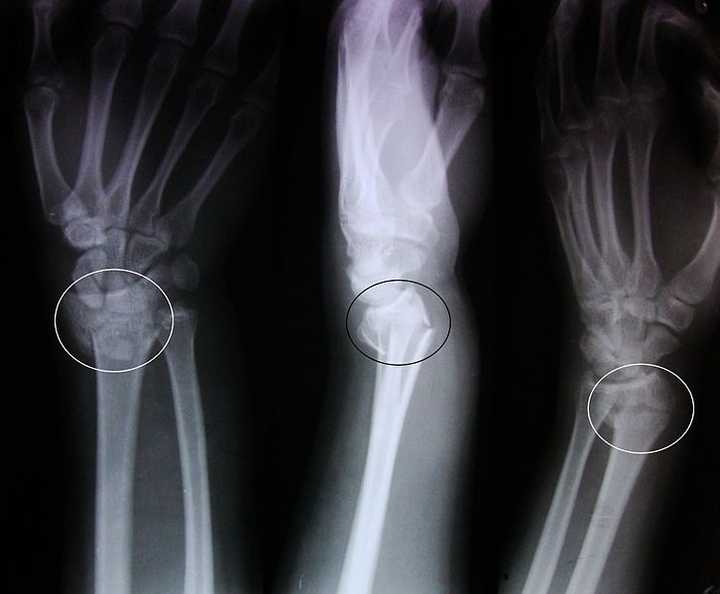

银叉样骨折

colles骨折

骨折)扩展阅读:来源丁香园骨科时间x线片正侧位示柯氏骨折图2银叉样

右腕关节肿胀明显,呈"银叉样"畸形,桡骨远端压痛( ),骨折断端可触及

远折端向背侧移位,侧面:银叉样smith骨折——屈曲型桡骨下段骨折小结